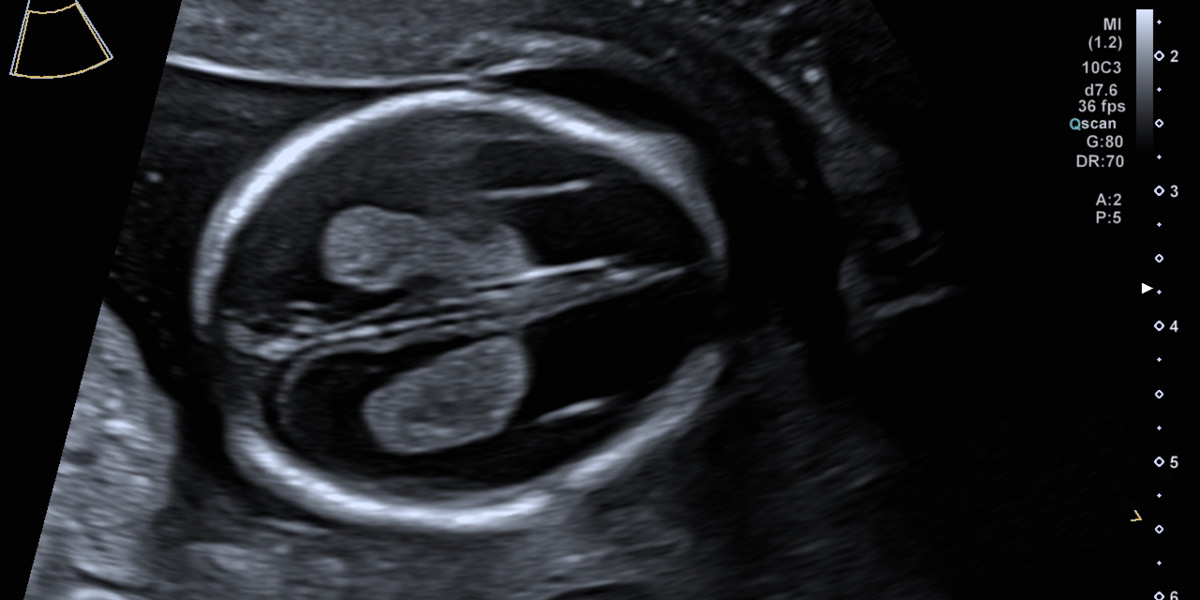

Bei der Nackentransparenzmessung sind auch Nasenbein und Hirnstrukturen sichtbar und geben unter anderem Aufschluss über die Wahrscheinlichkeit für Trisomie 21.

Kopfform und Großhirnhälften sind unauffällig entwickelt.